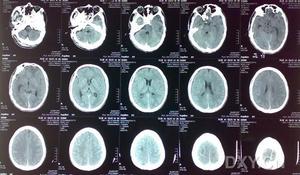

5.頭顱CT 掃描(CT) 臨床表現為腔隙性腦梗死的患者,CT 見有腔隙性梗死灶者占66%~76%。CT 對幕上>5mm 的腔隙病灶易於發現,而對<5mm 或位於腦幹的病灶常難以檢出。Rascal 等報導單純運動性輕偏癱綜合徵者,病後36h 檢查陽性率高達97%。一般病後10 天左右更易出現陽性改變。

(1)非增強掃描:病灶主要位於基底節區、丘腦、內囊、腦幹或放射冠、側腦室旁,呈圓形或橢圓形低密度灶,邊界清楚、直徑2~20mm,占位效應輕,一般僅為相鄰腦室受壓,多無中線結構移位。梗死區密度約於4 周后接近腦脊液密度,並呈現萎縮性改變,即同側側腦室和(或)鄰近腦池、腦溝局限性擴大,中線結構可有輕度的同側移位。

(3)多發性梗死痴呆的CT 掃描徵象:①腦皮質或皮質下多發的大小不一的低密度梗死灶,主要分布於基底節區及額、顳、枕葉皮質區。②大部分病例可呈腦萎縮改變,即腦室或腦溝擴大,腦皮質、髓質萎縮。③可伴有Binswanger 病(皮質下動脈硬化性白質腦病,SAE)CT 影像特徵:腦室周圍及半卵圓中心白質內的大致對稱性低密度影,呈月暈狀或傘狀,邊緣模糊,多位於側腦室前方或後方。灰/白質密度比值增加。